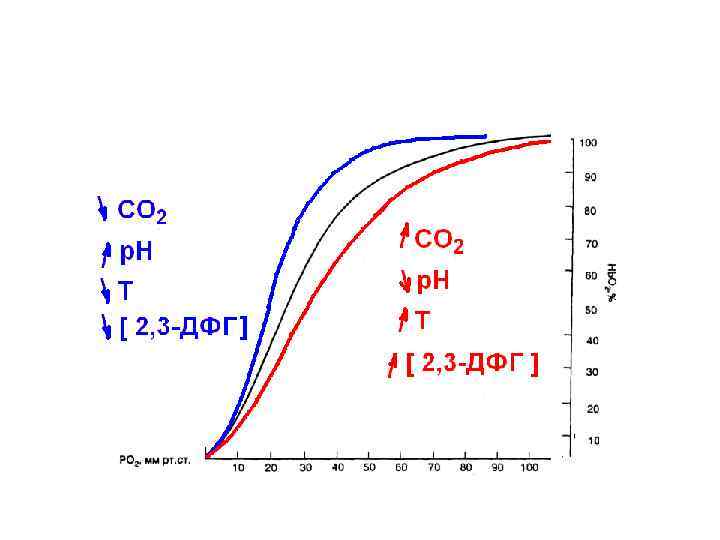

Вопрос 4 Кривая диссоциация оксигемоглобина

Вопрос 4 Кривая диссоциация оксигемоглобина